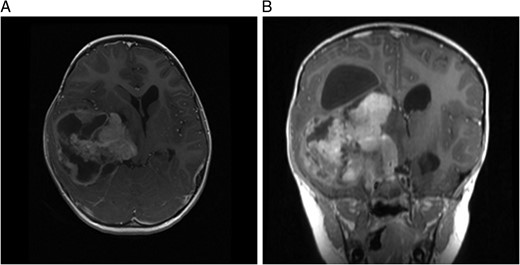

(A) MRI immediately following initial debulking of tumour showing a large subdural collection in a T2 FLAIR image and (B) coronal MRI post-op.

A computed tomography brain showed a large right temporoparietal cystic solid lesion with calcification and mass effect resulting in midline shift. A preoperative magnetic resonance imaging (MRI) brain and spine showed an enhancing lesion that extended to the occipital lobe, measuring 7 cm in maximum diameter (Fig. 1). A cystic lesion, measuring 5 × 8 cm was also identified posterosuperiorly. The medial part of the tumour extended to the thalami and lentiform nucleus. No spinal metastases were found.

MRI 1 month post-op showed that the residual tumour in the basal ganglia, which extended inferiorly to the cerebellar pontine region had grown slightly larger. Also noted was a subdural fluid collection overlying the right cerebral hemisphere with extension into the interhemispheric fissure. Further debulking was carried out on the residual tumour. An MRI immediately post-op showed only 8mm of the tumour lying adjacent to the brainstem remained, which had previously measured 5.2 cm.